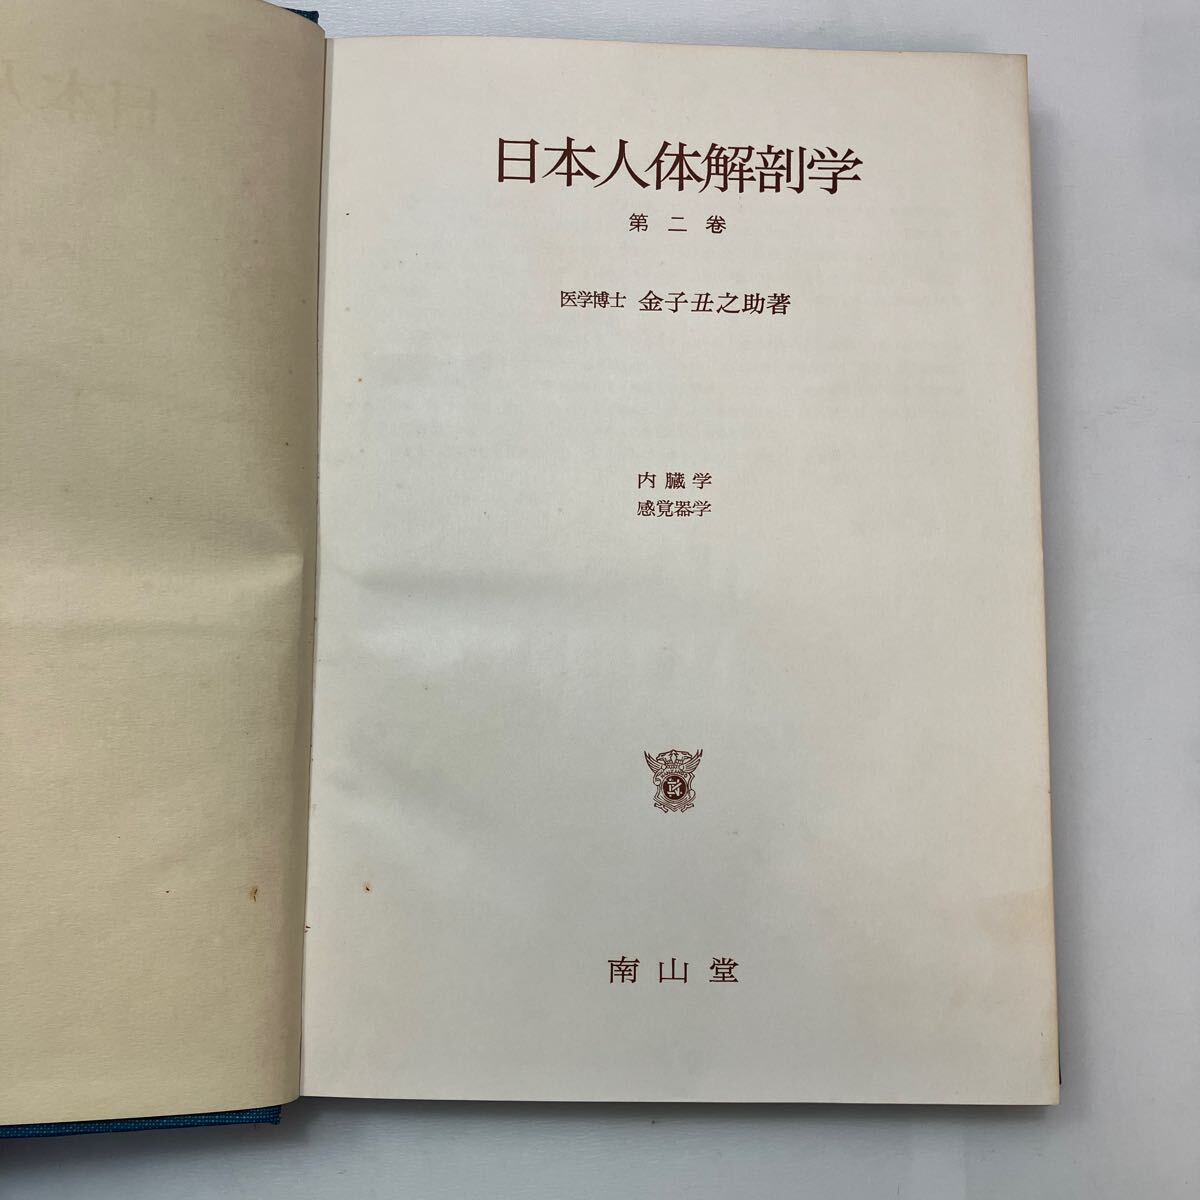

朝倉書店『内科学』(第12版)デジタル付録, zaa-598 日本人体解剖学 第2巻 内蔵学・感覚器学 改訂11版 金子,

zaa-598 日本人体解剖学 第2巻 内蔵学・感覚器学 改訂11版 金子, Amazon.co.jp: v∞ 明治期 皇国千字文解 上下巻 全2冊揃い 藤川,

f23122316〇明治11年 太陽暦 頒暦証付き〇和本古書古文書 / ひ, zaa-598 日本人体解剖学 第2巻 内蔵学・感覚器学 改訂11版 金子,

zaa-598 日本人体解剖学 第2巻 内蔵学・感覚器学 改訂11版 金子, 牛痘発蒙や虎狼痢治準ほか江戸期医学の和本(古典籍)を出張買取